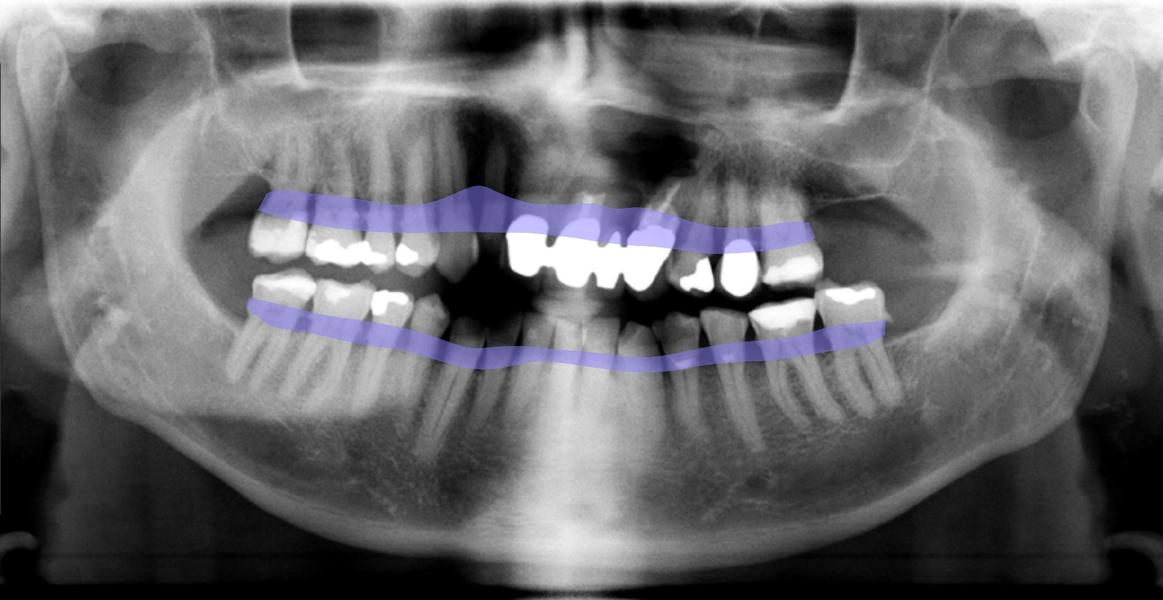

Panorama-Schichtaufnahme

Das „OPG“ wird bei der Aufnahme direkt in der EDV gespeichert und bietet uns einen Überblick über den gesamten Kieferbereich.Es bietet sehr viele diagnostische Möglichkeiten der Krankheitserkennung und auch der Implantatplanung.

DENTAL XRAI

Zahnarztpraxis Kirste setzt auf künstliche Intelligenz

Technisch ist unsere Zahnarztpraxis stets am Puls der Zeit. Daher freuen wir uns, dass wir jetzt auch zu den Ersten gehören, die bei der zahnmedizinischen Diagnostik auf das KI-unterstützte Tool dentalXrai setzen. Die aus der Berliner Charité entwickelte Software ermöglicht uns eine sichere automatisierte Analyse zahnmedizinischer Röntgenbilder – und zwar in Sekundenschnelle. Die Bestätigung der ärztlichen Befundung durch die KI-Lösung schafft zudem mehr Sicherheit und Vertrauen.

„Mit dem neuen Tool sparen wir nicht nur wertvolle Arbeitszeit, sondern können unsere Patienten noch besser in die Diagnose einbeziehen. Die Röntgenbilder zeigen wir ihnen ab sofort einfach am iPad, das Tool dentalXrai markiert hier Infektionen und Karies farbig. So sind Röntgenbilder und die Diagnose für jedermann leicht zu verstehen“, erklärt ZA Klaus Kirste die Beweggründe, dentalXrai in der Praxis einzuführen.

Die Röntgenbilder können im Anschluss dann einfach als PDF an unsere Patienten versendet werden.